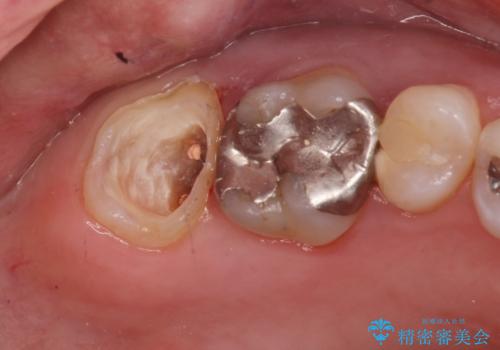

- 他院で右奥歯の治療が必要と言われて来院。

レントゲンと,CT撮影を行なったところ右上小臼歯が虫歯、右上第二大臼歯には根の先に大きな病気がありました。

手前の歯はセラミック治療を行い、奥の歯は精密根管治療を行いゴールドクラウンで治療を行いました。

セラミックインレーは古い材料を拡大鏡でしっかり取り除き適合の良い詰め物が装着されました。